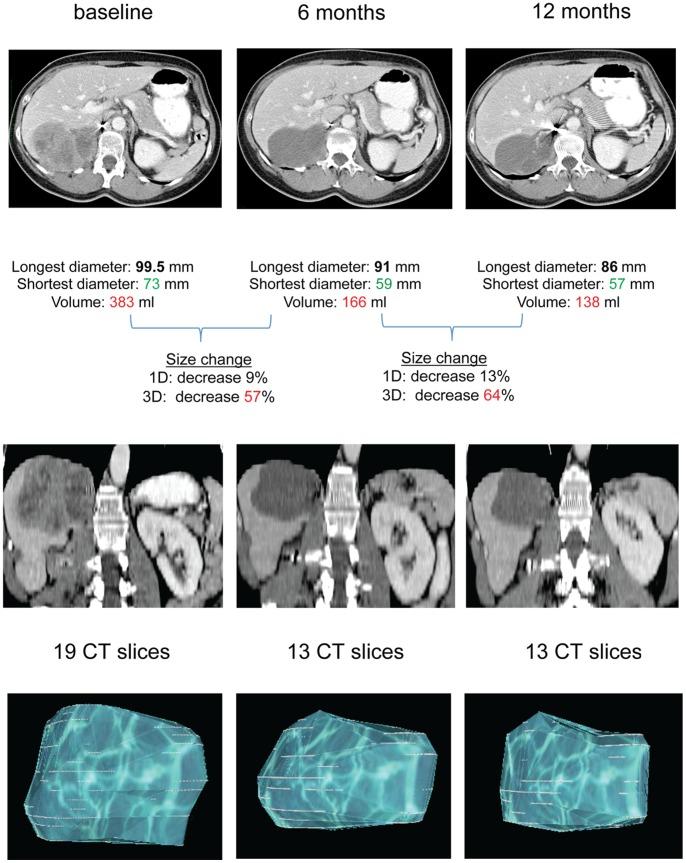

Assessment of tumor size changes is crucial in clinical trials and patient care. We compared imatinib-induced volume changes of liver metastases (LM) from gastro-intestinal stromal tumors (GIST) to RECIST and Choi criteria and their association with overall survival (OS).

LM from 84 GIST patients (training and validation set) were evaluated using manual and semi-automated Computed Tomography measurements at baseline, after 3, 6 and 12 months of imatinib. The ability of uni-dimensional (1D) and three-dimensional (3D) measurements to detect size changes (increase/decrease) ≥20% was evaluated. Volumetric response cut-offs were derived from minimally relevant changes (+20/-30%) by RECIST, considering lesions as spherical or ellipsoidal.

3D measurements detected size changes ≥20% more frequently than 1D at every time-point (P≤0.008). 3D and Choi criteria registered more responses than RECIST at 3 and 6 months for 3D-spheres (P≤0.03) and at all time-points for 3D-ellipsoids and Choi criteria (P<0.001). Progressive disease by 3D criteria seems to better correlate to OS at late time-points than other criteria.

Volume criteria (especially ellipsoids) classify a higher number of patients as imatinib-responders than RECIST. Volume discriminates size changes better than diameter in GIST and constitutes a feasible and robust method to evaluate response and predict patient benefit.